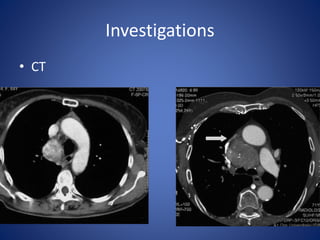

Investigations

• CT